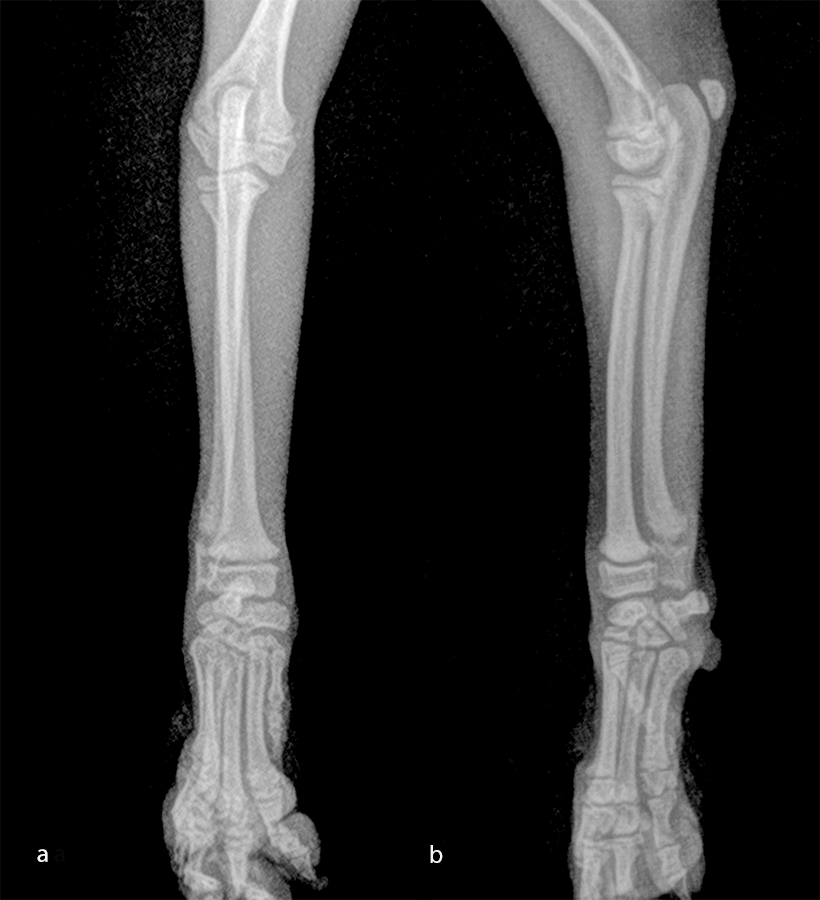

The patient was a 2.5-month-old, 1 kg Japanese Spitz dog presenting with a radial-ulna fracture of the left thoracic limb after a jump from the sofa. The LCP 1.3 T-plate was perfectly adapted for the distal radial fracture. As the dog was "active" and as the ulna was about the same size as the radius (Fig 11), a four-hole LCP 1.3 adaptation plate was used on the ulna.